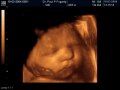

Images from the 3D & 4Dscan

3D/4D ultrasound is a new technology that allows you to see 3 dimensional colour images and videos of your unborn baby. With 3D/4D ultrasound you can actually see what your baby looks like before birth and you can see your baby move while it is still in the womb.

Good pictures of your baby can be obtained at any stage. In the early weeks you will see the whole baby moving its arms and legs but the details of the face are indistinct. Later in pregnancy you will see clearer images of your baby.

Between 18 and 34 weeks there is still plenty of fluid available to get a clear scan and the baby has started to "fatten up" making his or her facial features more as they would appear at birth. 3D/4D image quality depends on the baby’s position, size and movement.